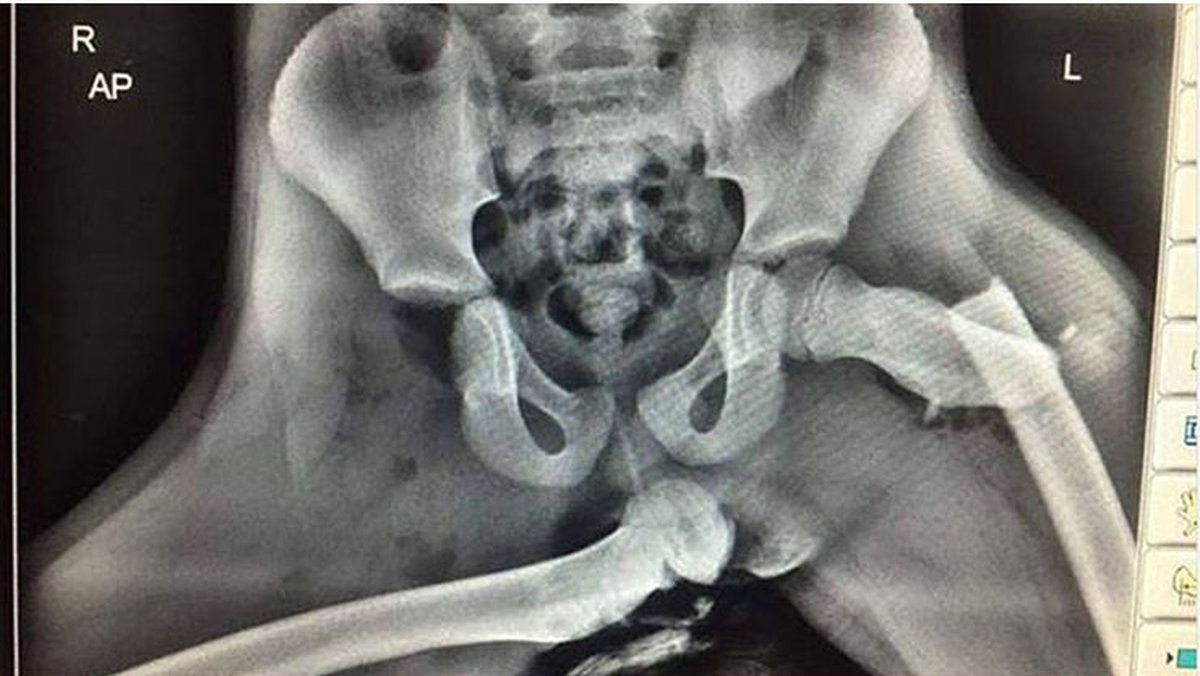

Όπως μπορείτε να δείτε από τη φωτογραφία που ακολουθεί σε μια πρόσκρουση ο αερόσακος του συνοδηγού ανοίγει και πιέζει με πολύ μεγάλη δύναμη τα πόδια. Οι επιπτώσεις μιας τέτοιας βίαιης μετακίνηση των ποδιών φαίνονται στην ακτινογραφία που έχει κυκλοφορήσει στο παρελθόν στο Twitter.

Όπως είπε χειρούργος ορθοπεδικός που είδε την ακτινογραφία στην αριστερή πλευρά υπάρχει κάταγμα του αυχένα του μηριαίου και στη δεξιά εξάρθρωση του μηρού. Παράλληλα η συγκεκριμένη στάση μπορεί να οδηγήσει και σε σοβαρό τραυματισμό του κεφαλιού, μιας και κινείται προς τα εμπρός και μπορεί να συγκρουστεί με τα πόδια που μετατοπίζονται βίαια προς τα πίσω.

Here is an X-ray of horrific injuries sustained to the front seat passenger who had their feet on the dashboard at the time of a collision. If you see your passenger doing it stop driving and show them this. pic.twitter.com/f3XCT8ePvi